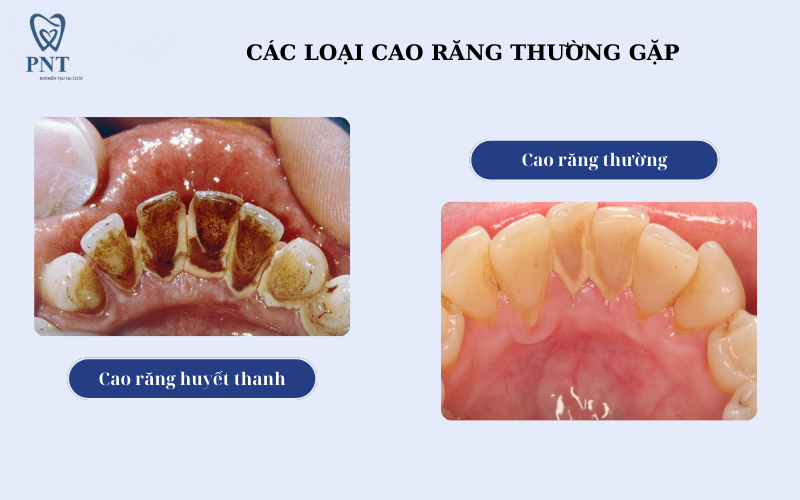

Cao răng có mấy loại?

Theo nha khoa, cao răng được chia thành 2 loại chính:

1. Cao răng thường (cao răng trên nướu)

-

Màu vàng nhạt hoặc trắng đục

-

Dễ nhìn thấy

-

Thường bám ở cổ răng

2. Cao răng huyết thanh (cao răng dưới nướu)

-

Màu nâu sẫm hoặc đen

-

Nằm sâu dưới nướu

-

Khó phát hiện bằng mắt thường

-

Gây viêm nha chu nghiêm trọng

Cao răng dưới nướu nguy hiểm hơn rất nhiều vì âm thầm phá hủy mô quanh răng và xương ổ răng.